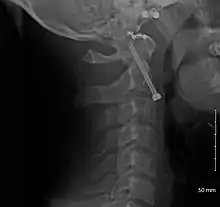

Fractures of the dens, not to be confused with Hangman's fractures, are classified into three categories according to the Anderson Alonso system:

- Type I fracture - Extends through the tip of the dens. This type is usually stable.

- Type II fracture - Extends through the base of the dens. It is the most commonly encountered fracture for this region of the axis. This type is unstable and has a high rate of non-union.

- Type III fracture - Extends through the vertebral body of the axis. This type can be stable or unstable and may require surgery.

A fracture of the base of the dens as seen on plain X-ray